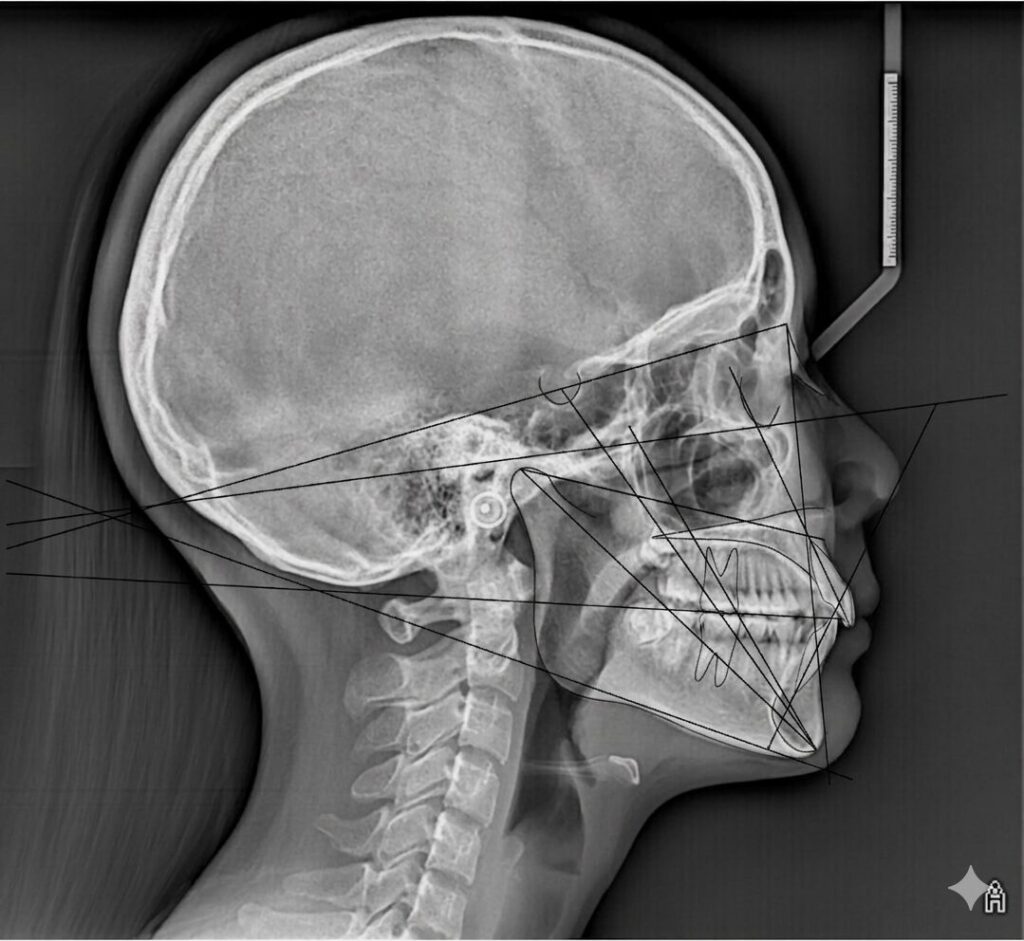

Ceph-iQ (Aust).

A dedicated Cephalometric Tracing Service

We offer ther following Analysis Types:

Jefferson

Steiner

Ricketts

Mahony

Downs

Bjork – Jarabak

IBO

Wits

Sassouni

Segner – Hasound

Tweed

Bondi

Skoumbri